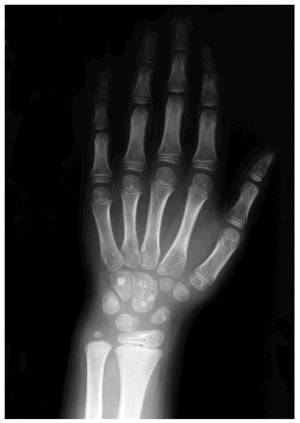

En la exploración física presentaba varias placas de color blanco-amarillento, de varios centímetros de diámetro, localizadas en la cadera izquierda (fig. 1), brazo izquierdo, muslos derecho e izquierdo, tobillo izquierdo y cara posterior de tórax. El resto de la exploración física fue normal, sin observarse datos de inflamación, deformidad, ni limitación de la movilidad articular. El estudio histológico con hematoxilina-eosina de una lesión cutánea no mostró alteraciones histológicas relevantes. En el estudio de fibras elásticas con tinción de orcenía se observó un incremento en el número y en el grosor de las fibras elásticas en la dermis reticular compatible con nevo elástico (fig. 2).

Fig. 2.--Aumento del grosor de las fibras elásticas en la dermis reticular. (Tinción con orceína, x100.)

El síndrome de Buschke-Ollendorf es una enfermedad hereditaria, autosómica dominante con expresividad variable, cuya incidencia se estima2 en torno a 1/20.000. El síndrome asocia lesiones cutáneas del tipo nevos elásticos diseminados y osteopoiquilia. Existen dos formas de presentación clínica cutánea; bien como múltiples pápulas liquenoides, milimétricas, asintomáticas, distribuidas simétricamente, conocida como «dermatofibrosis lenticularis disseminata», o bien a modo de nódulos, color piel o amarillentos, solitarios o agrupados formando placas3-6, de distribución generalmente asimétrica, en tronco y extremidades. Las lesiones suelen aparecer en las primeras décadas de la vida, aunque pueden estar presentes desde el nacimiento7. Una vez aparecidas tienden a permanecer estables8. Desde el punto de vista histológico se observa una piel prácticamente normal con hematoxilina-eosina, pero con tinciones específicas para las fibras elásticas se observan en la mayoría de los casos unas fibras elásticas alargadas, engrosadas y entrelazadas en dermis reticular9.